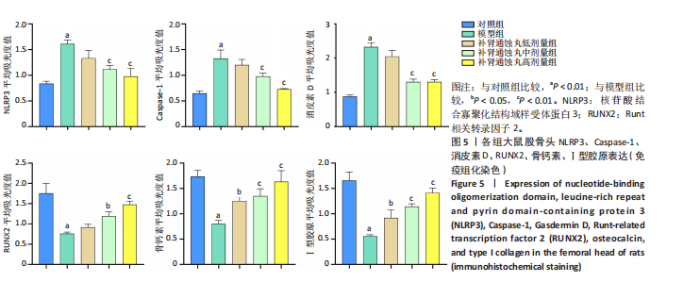

.1 实验动物数量分析 参加实验SD大鼠数量为50只,均进入结果分析。 2.2 Micro-CT检测结果 通过Micro-CT观察各组大鼠股骨头区域骨质变化,见图1。乙醇会导致大鼠股骨头软骨下骨骨量明显减少,骨小梁排列出现紊乱、稀疏等状况,而补肾通蚀丸能够改善上述情况,且呈现一定的剂量效应。模型组骨小梁厚度、骨小梁数目、骨体积分数、骨密度较对照组显著降低(P < 0.01),模型组骨小梁间隙较对照组则显著升高(P < 0.01)。经过不同剂量补肾通蚀丸干预后,各项指标均出现不同程度的逆向改变;其中,与模型组比较,补肾通蚀丸高剂量组骨小梁厚度、骨小梁数目、骨体积分数、骨密度均显著升高(P < 0.05),骨小梁间隙则显著降低(P < 0.05);与模型组比较,补肾通蚀丸中剂量组骨体积分数、骨密度显著升高(P < 0.05),骨小梁间隙则显著降低(P < 0.05);而补肾通蚀丸低剂量组仅在骨小梁间隙指标上较模型组显著降低(P < 0.05),见图2。 2.3 苏木精-伊红染色结果 与对照组比较,模型组大鼠股骨头出现核固缩现象,多见脂肪空泡,部分骨小梁出现断裂、变细;补肾通蚀丸低、中、高剂量组骨细胞核固缩和脂肪空泡较模型组有所减少;在整体结构方面,补肾通蚀丸低剂量组骨小梁变细现象较模型组未见明显改善,但断裂情况有所改善;而补肾通蚀丸中、高剂量组骨小梁断裂、变细情况较模型组均明显改善,见图3;在空骨陷窝率方面,模型组较对照组显著增高(P < 0.01);补肾通蚀丸中、高剂量组较模型组有所降低(P < 0.05),见图3。 2.4 免疫组化染色结果 与对照组比较,模型组NLRP3、Caspase-1、消皮素D蛋白表达明显增强,而Runt相关转录因子2、骨钙素、Ⅰ型胶原蛋白表达显著降低(P < 0.01);与模型组比较,补肾通蚀丸中、高剂量组能够显著降低NLRP3、Caspase-1、消皮素D蛋白表达,且促进Runt相关转录因子2、骨钙素、Ⅰ型胶原蛋白表达(P < 0.05),而补肾通蚀丸低剂量组骨钙素、Ⅰ型胶原蛋白表达有所上调(P < 0.05),其余指标则无明显差异(P > 0.05),见图4,5。 2.5 ELISA检测结果 与对照组比较,模型组大鼠血清中白细胞介素18和白细胞介素1β水平显著增高(P < 0.01);与模型组比较,补肾通蚀丸各剂量组大鼠血清中白细胞介素18和白细胞介素1β水平均显著降低(P < 0.01),且以一定剂量依赖方式递减,见图6。 2.6 Western blot检测结果 与对照组比较,模型组大鼠股骨头组织中NLRP3、cleaved-Caspase-1、Caspase-1、消皮素D、消皮"

素D-N蛋白表达均显著上调(P < 0.01),成骨因子Runt相关转录因子2、骨钙素、Ⅰ型胶原蛋白表达均显著下调(P < 0.05);补肾通蚀丸各剂量组NLRP3、cleaved-Caspase-1、Caspase-1、消皮素D、消皮素D-N蛋白表达以一定剂量依赖方式呈现不同程度的下调,Runt相关转录因子2、骨钙素、Ⅰ型胶原蛋白表达则以一定剂量依赖方式呈现不同程度的上调;与模型组比较,补肾通蚀丸中、高剂量组NLRP3、cleaved-Caspase-1、Caspase-1、消皮素D、消皮素D-N蛋白表达均显著下调(P < 0.05),补肾通蚀丸高剂量组Runt相关转录因子2、骨钙素、Ⅰ型胶原表达均显著上调(P < 0.01),补肾通蚀丸中剂量组Runt相关转录因子2蛋白表达显著上调,而骨钙素、Ⅰ型胶原表达无明显差异(P > 0.05),补肾通蚀丸低剂量组Runt相关转录因子2、骨钙素、Ⅰ型胶原表达均无明显差异(P > 0.05),见图7A,B。与对照组比较,模型组cleaved-Caspase-1/Caspase-1比值和消皮素D-N/消皮素D比值均显著上升(P < 0.01);与模型组比较,补肾通蚀丸中、高剂量组cleaved-Caspase-1/Caspase-1比值和消皮素D-N/消皮素D比值均显著下降(P < 0.01),而补肾通蚀丸低剂量组cleaved-Caspase-1/Caspase-1比值与对照组比较无明显差异(P > 0.05),见图7C。 2.7 RT-qPCR检测结果 RT-qPCR结果显示,与对照组比较,模型组大鼠股骨头组织中NLRP3、Caspase-1、消皮素D mRNA表达显著上调,Runt相关转录因子2、骨钙素、Ⅰ型胶原mRNA表达显著下调(P < 0.01);与模型组比较,补肾通蚀丸中、高剂量组NLRP3、Caspase-1、消皮素D mRNA表达均显著下调,Runt相关转录因子2、骨钙素、Ⅰ型胶原mRNA表达均显著上调(P < 0.01),而补肾通蚀丸低剂量组NLRP3、Caspase-1、Runt相关转录因子2、骨钙素mRNA表达均无明显差异(P > 0.05),见图8。"